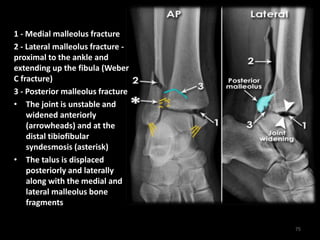

Trimalleolar fracture - AP

and Lateral

74

1 - Medial malleolus fracture

2 - Lateral malleolus fracture -

proximal to the ankle and

extending up the fibula (Weber

C fracture)

3 - Posterior malleolus fracture

• The joint is unstable and

widened anteriorly

(arrowheads) and at the

distal tibiofibular

syndesmosis (asterisk)

• The talus is displaced

posteriorly and laterally

along with the medial and

lateral malleolus bone

fragments

75